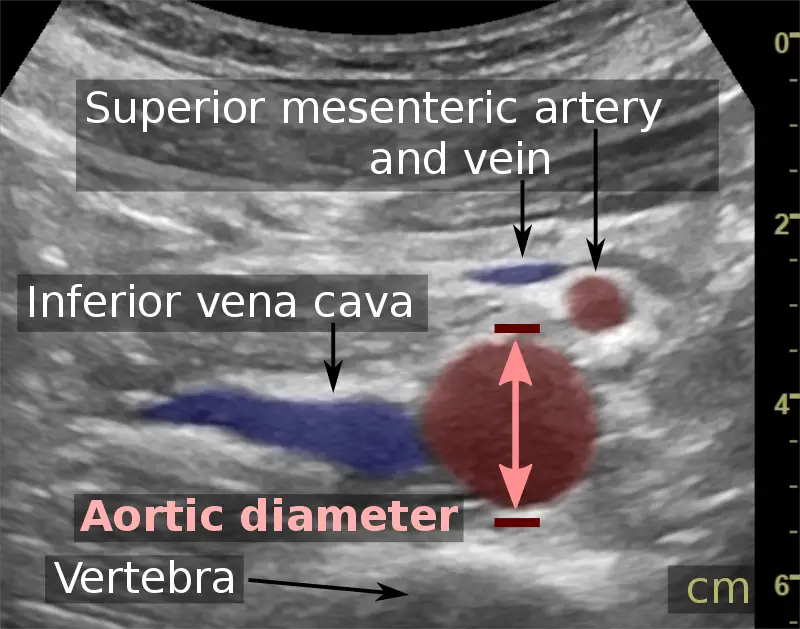

Abdominal Aortic Aneurysm

Abdominal aortic aneurysm (AAA) is an aneurysm of the abdominal aorta.

Abdominal aortic aneurysm typically develops above the aortic bifurcation but below the renal arteries.

Abdominal aortic aneurysm (AAA) is typically associated with hypertension and atherosclerosis.

Abdominal aortic aneurysm (AAA) typically presents with a triad of:

- Flank pain

- Pulsating abdominal mass

- Hypotension

Symptoms of abdominal aortic aneurysm include an abdomen lump that pulses initially and enlarges over time.